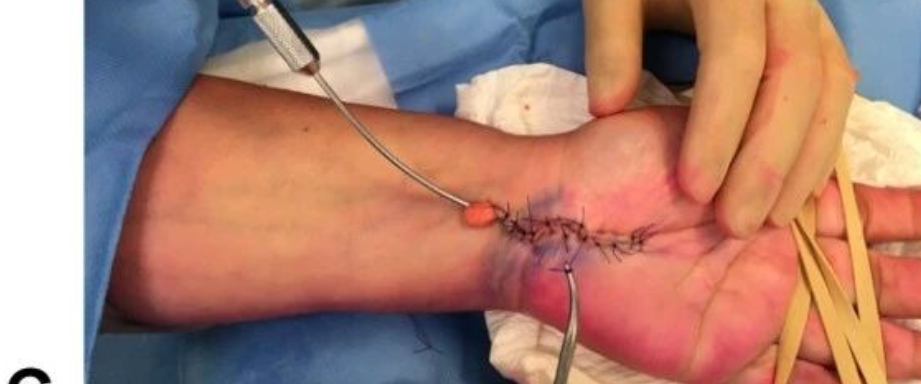

手外伤处理原则专题课程

71分钟

3.6万人学习